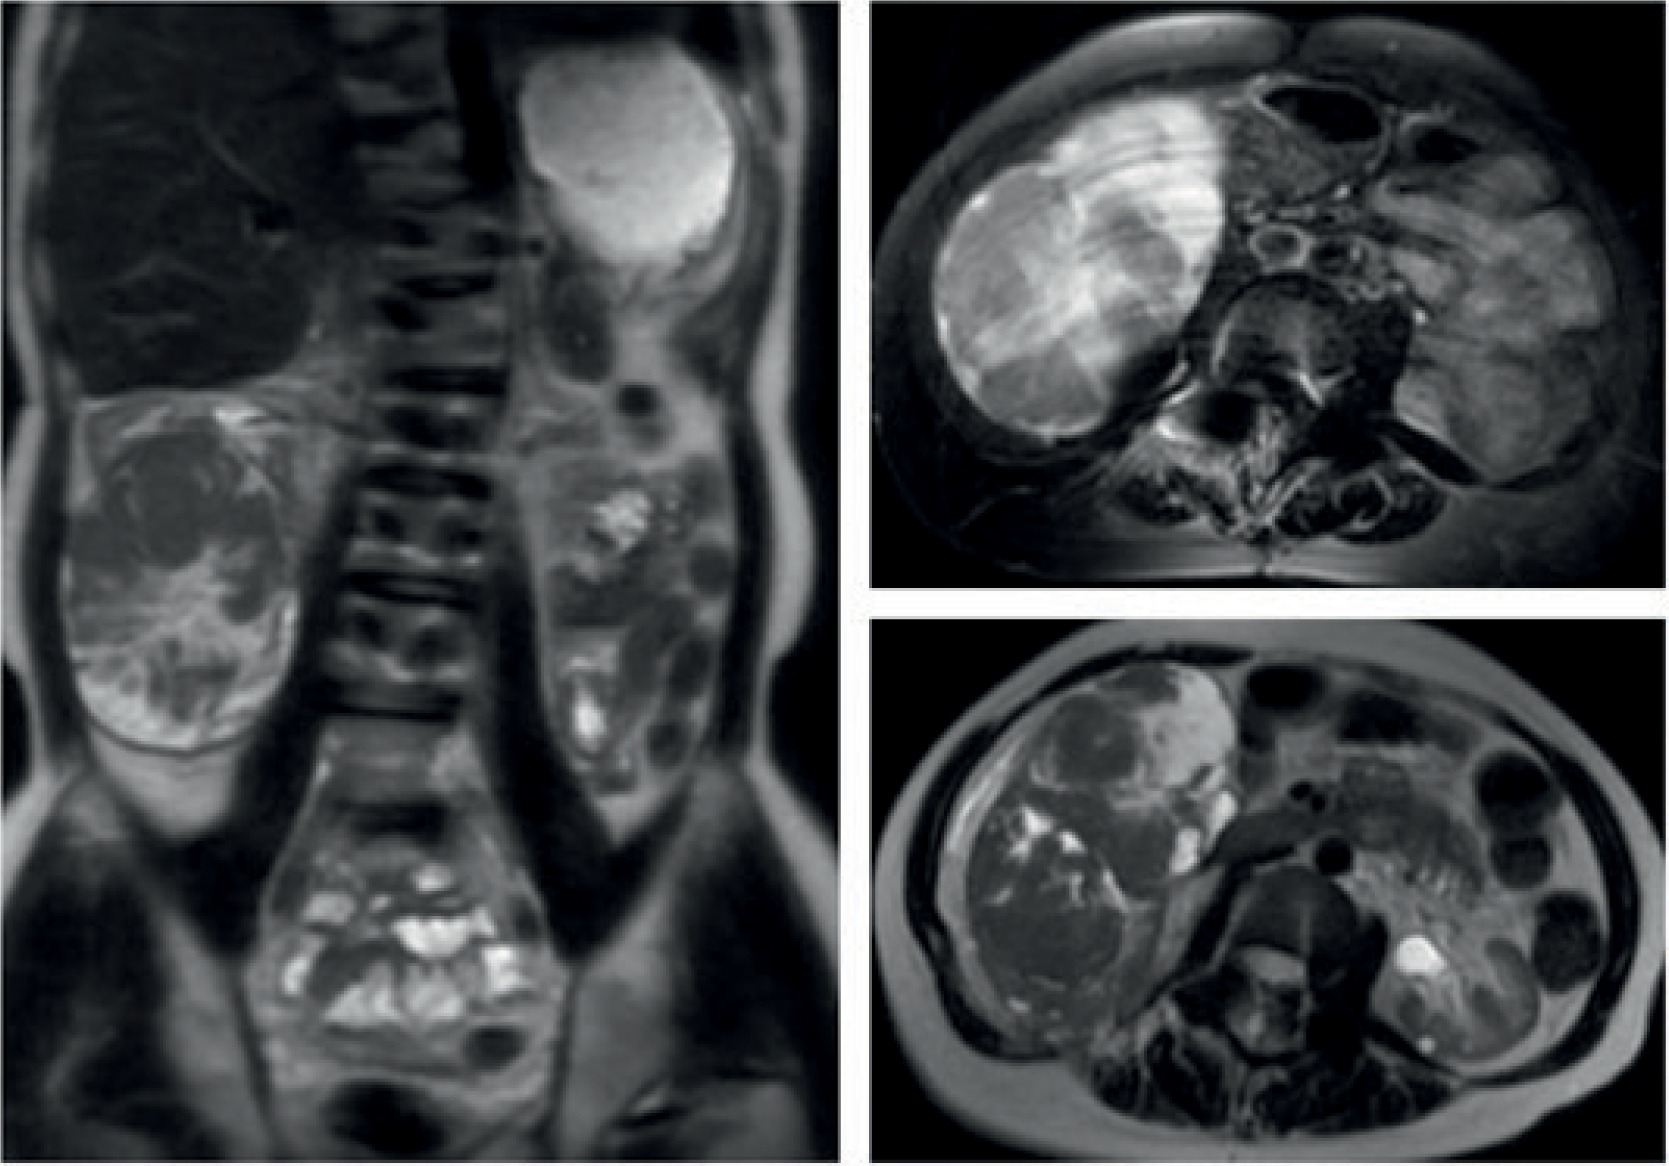

A 30-year-old male presented with a large right renal mass, discovered on renal ultrasound (US) performed due to a recent rise in creatinine levels from 2.0 mg/dL to 2.56 mg/dL with an estimated glomerular filtration rate (GFR) of 34. The renal ultrasound revealed a solid and heterogenous renal mass appearing 11.3 × 7.5 × 12.6 cm right side. He denied urinary complaints but noted vague abdominal discomfort. His past medical history included Jeune syndrome (asphyxiating thoracic dystrophy), chronic kidney disease (CKD), hypertension, hypercholesterolemia, retinitis pigmentosa, asthma, attention deficit hyperactivity disorder (ADHD), scoliosis, and obstruction of posterior urethral valves as well as a right uretero pelvic junction, both of which were repaired during childhood. His brother also had a past medical history of Jeune syndrome with renal failure, which required a kidney transplant. The family history was notable for appendiceal adenocarcinoma in his mother and prostate cancer in his father. The patient underwent a left renal biopsy as a toddler because of renal insufficiency, which revealed no gross abnormalities, and another renal biopsy at 29 years of age, revealing mesangial hyperplasia with focal glomerulosclerosis consistent with C1q nephropathy. Following the renal ultrasound, further work up with chest X-ray showed no evidence of metastases; however, magnetic resonance imaging (MRI) of the abdomen and pelvis without intravenous (IV) contrast revealed an 11.6- × 8.3- × 12.7-cm right lower pole mass with little normal kidney remaining (Figure 1).

Figure 1: MRI imaging of abdomen without IV contrast: Multiplanar T1- and T2-weighted images of the abdomen were obtained without IV contrast. A large and complex mass is seen arising from the right kidney lower pole measuring 11.6 × 8.3 × 12.7 cm.